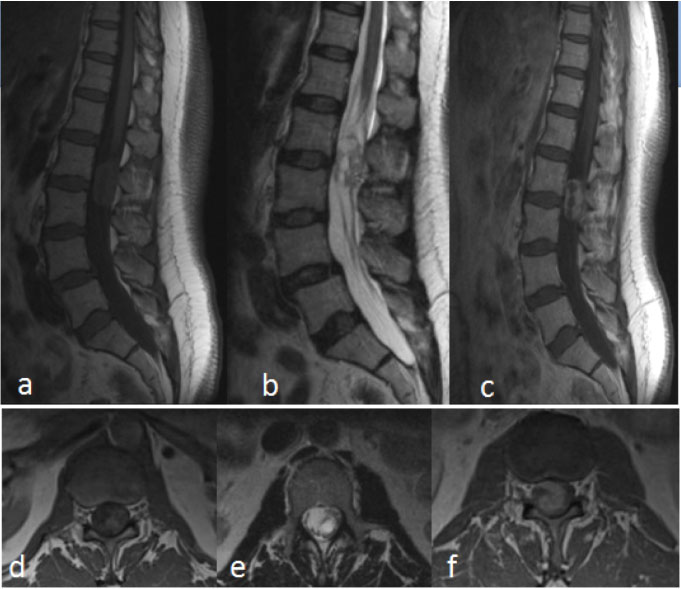

Figure 5: Myxopapillary ependymoma.

MRI Lumbar spine a) Sagittal T1; b) Sagittal T2 FSE; c) Sagittal T1 post-contrast; d) Axial T1; e) Axial T2 FSE; f) Axial T1 post-contrast.

59-year-old woman, presents with increasing pain radiating down the right leg, some bladder hesitancy, but no weakness of lower extremities. MRI of the lumbar spine shows a 5 × 2 × 1.5 cm heterogeneously enhancing mass with cystic components. The tumor was located in the filum terminale from L1 to L3. Surgical pathology was consistent with myxopapillary ependymoma.

Myxopapillary ependymomas are typically lobular, often encapsulated, and contain gelatinous material [13]. They may have cyst formation and hemorrhage [13]. These typically occur in the extradural space, [2] compared to the intramedullary location of other spinal ependymomas. These lesions are best characterized on MRI imaging and are usually isointense relative to the spinal cord on T1 weighted images and hyperintense on T2 weighted images [14]. If there is hyperintensity within the lesion on both T1 and T2 weighted images, it likely reflects its mucin or hemorrhagic content. Myxopapillary ependymomas enhance after the administration of intravenous gadolinium. The location of these tumors within the conus medullaris suggests this diagnosis [15] (Figure 5).